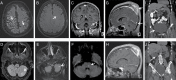

Figures